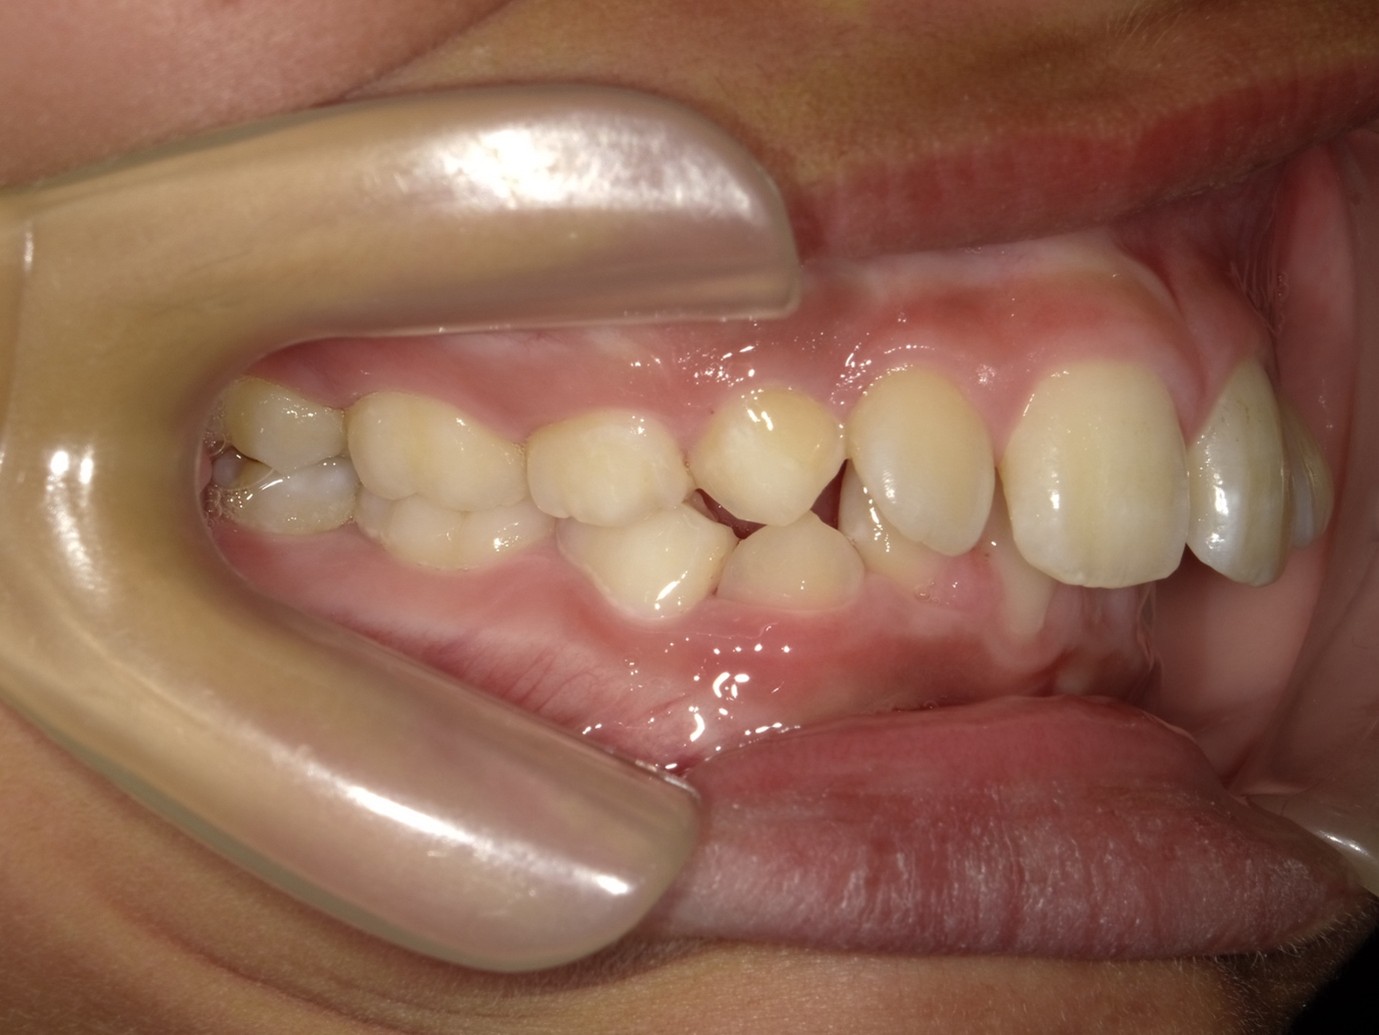

| 症例分類 | 過蓋咬合 |

|---|---|

| 主訴 | 他の歯科医院で咬み合わせを指摘された |

| 年齢 | 10歳10ヶ月 |

| 性別 | 男性 |

| 抜歯部位 | なし |

| 使用装置 | 拡大装置、咬合斜面板(取り外し式の矯正装置) |

| 治療期間 | 3年4ヶ月 |

| 保定装置 | 咬合斜面板 |

| 費用 | 相談料0円、検査料55,000円 動的矯正治療費330,000円 調整料6,600円×30回分 保定装置料0円 |

| リスク・注意点 | 上の顎の大きさに対して下の顎が小さく、過蓋咬合が生じています。これらを改善するために、幅の狭搾している歯列を側方に拡大したのち、下顎の成長を促進しました。

歯の動き方には個人差があり、予想された治療期間が延長する可能性があります。 治療中は矯正歯科装置が歯の表面に付いており、歯が磨きにくくなるため、むし歯や歯周病が生じるリスクが高まります。ハミガキを適切に行ってお口の中を常に清潔に保ち、さらに、かかりつけ歯科医に定期的に受診することが大切です。 矯正歯科装置の使用状況、定期的な通院など、矯正歯科治療には患者さんの協力が必要であり、それらが治療結果や治療期間に影響します。 治療の経過によっては当初予定していた治療計画を変更する可能性があります。保定装置の装着時間が十分確保できない場合、歯並びや、咬み合せの「後戻り」が生じる可能性があります。 上下両側第二大臼歯の萌出を観察する必要があります。(治療後の写真は成人矯正開始直前の資料です。) |